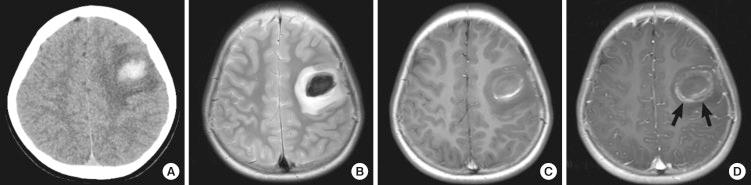

Paragonimiasis is caused by ingesting crustaceans, which are the intermediate hosts of Paragonimus. The involvement of the brain was a common presentation in Korea decades ago, but it becomes much less frequent in domestic medical practices. We observed a rare case of cerebral paragonimiasis manifesting with intracerebral hemorrhage. A 10-yr-old girl presented with sudden-onset dysarthria, right facial palsy and clumsiness of the right hand. Brain imaging showed acute intracerebral hemorrhage in the left frontal area. An occult vascular malformation or small arteriovenous malformation compressed by the hematoma was initially suspected. The lesion progressed for over 2 months until a delayed surgery was undertaken. Pathologic examination was consistent with cerebral paragonimiasis. After chemotherapy with praziquantel, the patient was monitored without neurological deficits or seizure attacks for 6 months. This case alerts practicing clinicians to the domestic transmission of a forgotten parasitic disease due to environmental changes.